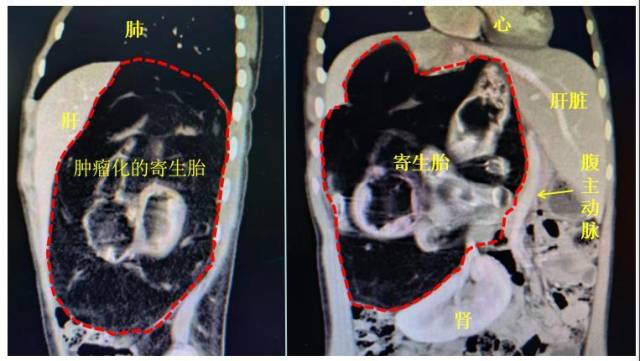

肺肾肝多器官受压

小邱入院后,住进了温馨的胃肠肿瘤中心病房,并很快接受了各项检查。术前CT提示,肿瘤位于右肝后方的腹膜后区域,考虑为体内巨大寄生胎,直径达25厘米。由于该寄生胎早已死亡,呈肿瘤性生长,肿瘤将下腔静脉向前包绕、推挤达前腹壁附近,将腹主动脉向左侧严重向左侧推挤。肝脏被肿瘤严重挤压成不规则的镰刀型,右侧肾脏被挤压向下呈三角形,肾脏血管无法分辨。膈肌也被明显向上挤压、上抬,导致右肺受到严重挤压,右肺功能受到损害。